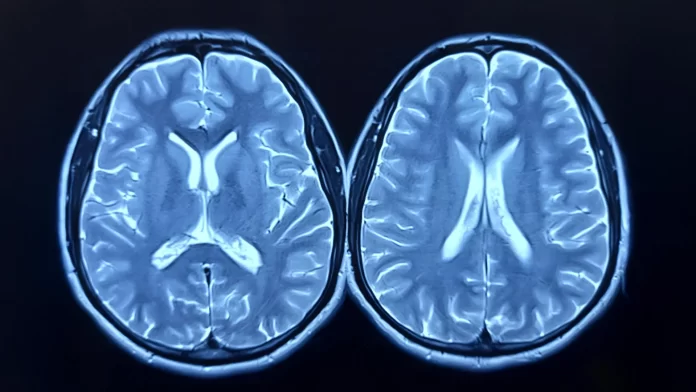

The research team looked at longitudinal brain scans from nearly 1,000 healthy adults, taken as part of the UK Biobank study. Some participants had scans before and after the pandemic; others, only before. Using advanced imaging and machine learning, the researchers estimated each person’s “brain age” — how old their brain appeared to be compared to their actual age.

The brain age model was developed using brain scans from over 15,000 healthy individuals, without comorbidities, allowing the researchers to build an accurate model for estimating brain age.

Stamatios Sotiropoulos, Professor of Computational Neuroimaging, and co-lead author added: “The longitudinal MRI data acquired before and after the pandemic from the UK Biobank gave us a rare window to observe how major life events can affect the brain.”